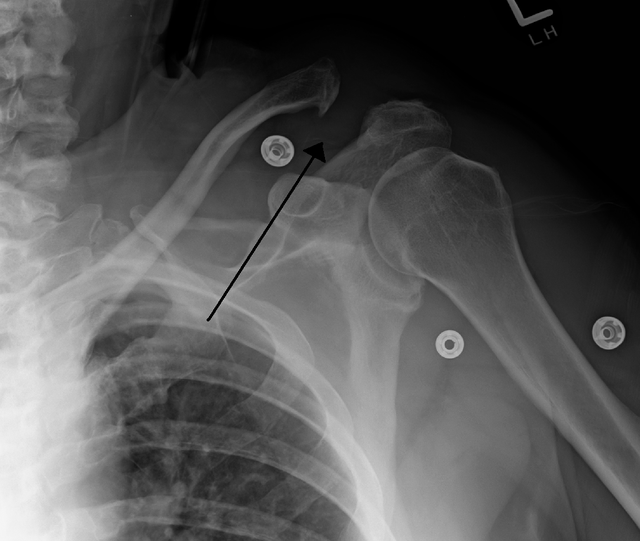

Example 5

Diagnosis

Acromioclavicular Joint Dislocation

Image 5: James Heilman, MD ACseperation.png consolidation. Case study, Radiopaedia.org. (accessed on 11 Oct 2022) https://doi.org/10.53347/rID-7393